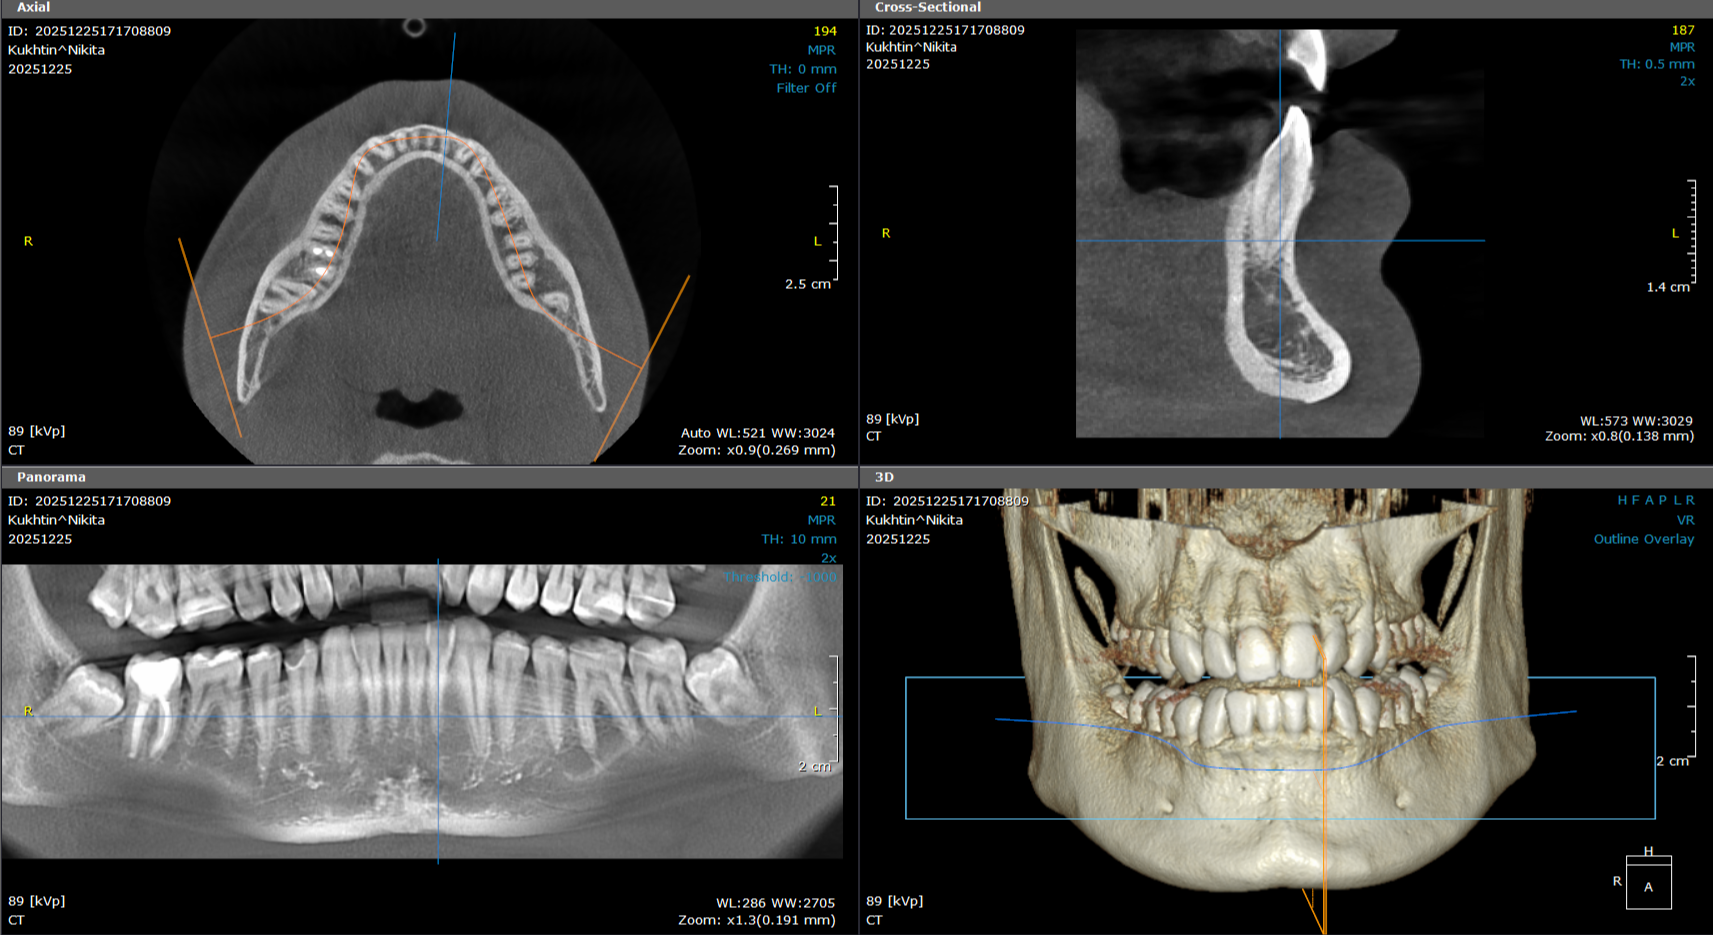

3D snimanje zuba predstavlja savremenu dijagnostičku metodu u stomatologiji koja omogućava trodimenzionalni prikaz zuba, vilice i okolnih anatomskih struktura. Ova tehnologija, poznata kao CBCT (Cone Beam Computed Tomography), pruža izuzetno precizne informacije koje stomatolozima pomažu u planiranju terapije i izvođenju složenih stomatoloških procedura.

Za razliku od klasičnih 2D snimaka, 3D snimci omogućavaju detaljan prikaz kosti, položaja zuba, nervnih kanala i sinusa, što je posebno važno kod planiranja ugradnje implantata, ortodontske terapije, endodontskog lečenja i hirurških intervencija.

DIJAGNOSTIKA KORENSKIH KANALA

Kod komplikovanih slučajeva lečenja zuba, 3D snimanje pruža detaljan uvid u strukturu korena.

Jedna od najvećih prednosti 3D snimanja zuba je izuzetna preciznost i mogućnost analize svakog detalja. Za razliku od tradicionalnih 2D snimaka, gde se strukture preklapaju, 3D tehnologija omogućava slojevito prikazivanje zuba, kostiju i okolnih anatomskih struktura.

To znači da stomatolog može jasno da vidi položaj živaca, debljinu kosti i potencijalne komplikacije pre same intervencije. Na taj način se smanjuje rizik i povećava sigurnost svakog zahvata, posebno kada je u pitanju ugradnja implantata ili složeniji hirurški zahvati.